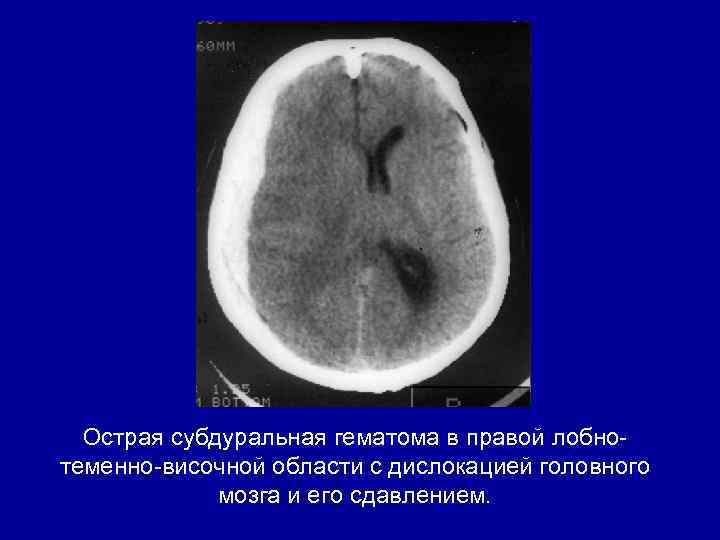

Острая субдуральная гематома в правой лобнотеменно-височной области с дислокацией головного мозга и его сдавлением.

Острая субдуральная гематома в правой лобнотеменно-височной области с дислокацией головного мозга и его сдавлением.